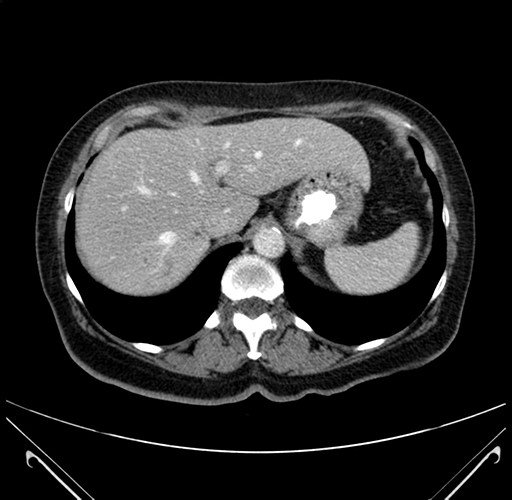

Pre-Chemo: Axial Venous

Axial Venous